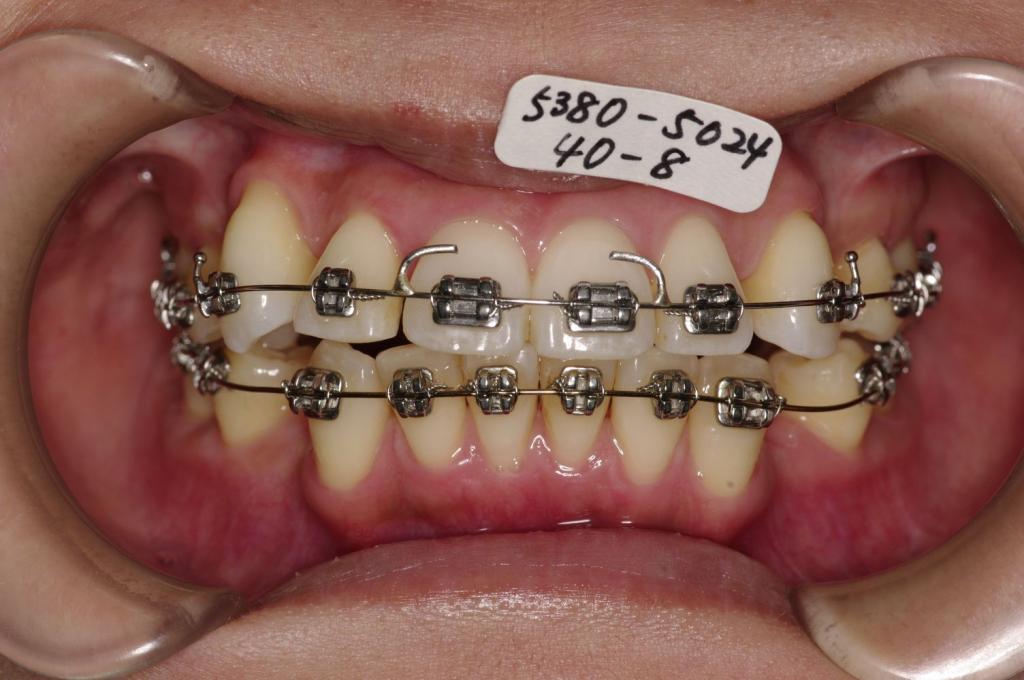

- 上下の前歯の間に舌を入れる癖がある場合には、歯の裏側にフックを付ける場合があります。その場合発音がしにくくなったり、食事の時に舌が痛かったりすることがあります。